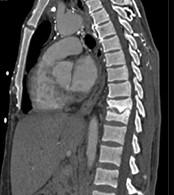

问题 男,36岁,腰背部疼痛,局部软组织肿胀,夜间加重,背部有过外伤史,有过结合图像,最可能的诊断是 ( )

选项 A、强直性脊柱炎 B、结核性骨髓炎 C、硬化型骨肉瘤 D、慢性骨髓炎 E、骨样骨瘤

答案 D